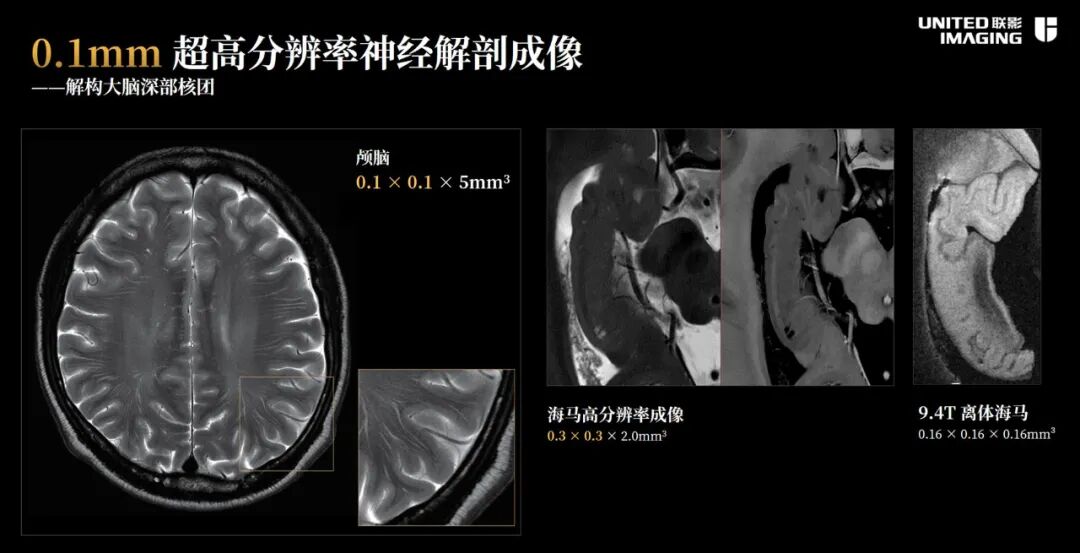

790探索3.0T磁共振是由联影完全自主设计、研发的一款高性能科研型3.0T磁共振平台,所有核心部件完全自研,其具备的超高性能和稳定性在神经科研、全身临床领域有着极大的突破性应用潜力。该设备所搭载的超高性能梯度与百亿分之三偏离度的超高均匀度磁体,性能达到国际脑科学研究行业标准。借助其超高性能和超高稳定性,该设备也成为建设中国人脑图谱影像大数据平台的关键技术支撑和指定研究平台。而这也是国产高端医学影像设备首次应用于国家脑科学研究这样前沿重大科研项目。